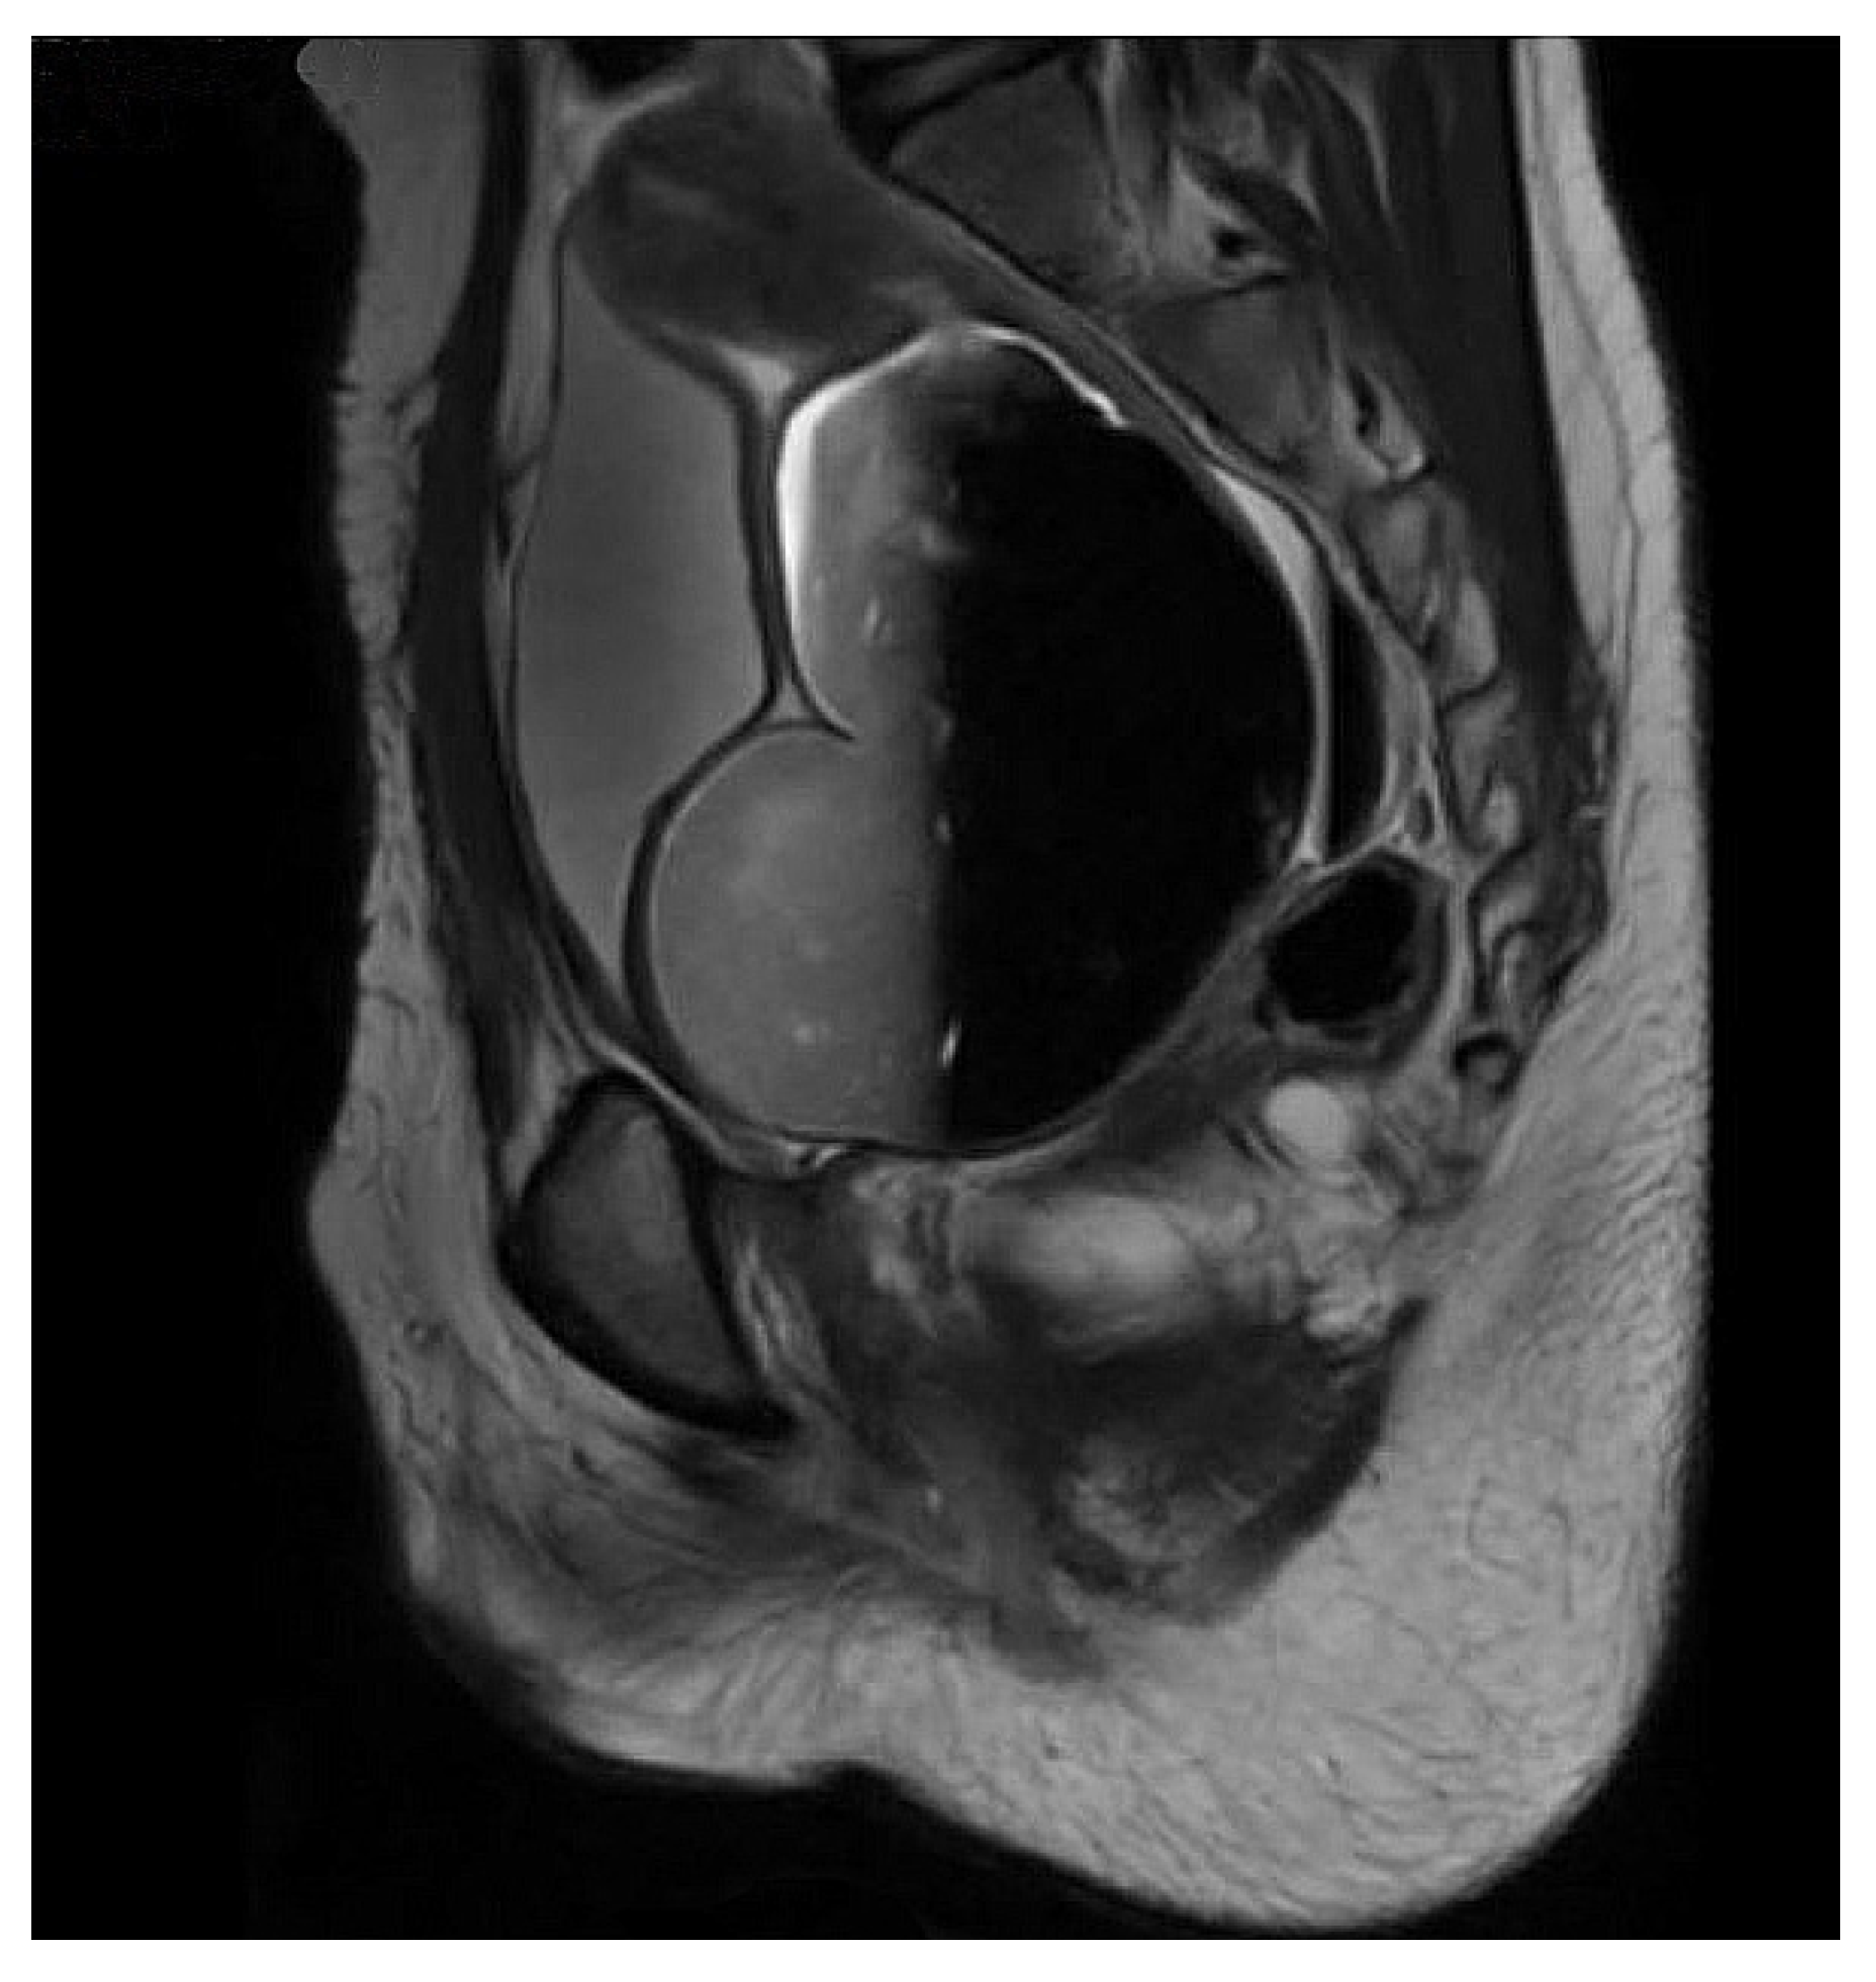

Figure 2.

MRI showing grossly dilated vagina and hematocolpos in a patient with prior repair of pelvic fracture urethral injury.